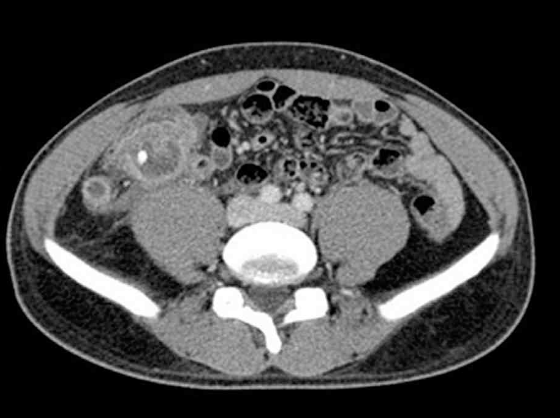

35세 남자가 8일 전부터 배가 아파서 병원에 왔다. 3일 전부터 아랫배에서 덩이가 만져진다고 한다. 혈압 130/70 mmHg, 맥박 100회/분, 호흡 22회/분, 체온 38.1°C이다. 오른쪽 아랫배에서 어린이 주먹 크기의 덩이가 만져지고, 오른쪽 아랫배에 압통과 반동압통이 있다. 혈액검사 결과는 다음과 같다. 복부 컴퓨터단층촬영 사진이다. 진단은?

CT: Fluid collection and inflammatory change in appendix, appendicolith

Imp: 충수주위고름집(periappendiceal abscess)

치료 받지 않은 막창자꼬리염 환자에서 CT상 농양이 확인되므로 충수주위고름집을 진단할 수 있다.

• 복부 CT에서 막창자꼬리 부위에 염증성 변화를 동반한 액체 저류와 appendicolith가 관찰된다. 막창자꼬리염은 3일 이내 수술받지 않으면 파열될 가능성이 높으며, 터지게 된다면 고름이 고여 농양을 형성하거나 복막염으로 진행할 수 있다.

• 따라서 해당 소견을 종합하여 볼 때 8일 전 급성 막창자꼬리염이 발생하였으나 적절한 시기에 치료받지 못하여 천공이 생겼고, 이로 인해 고름이 고여서 충수주위고름집을 형성한 것으로 판단할 수 있다.